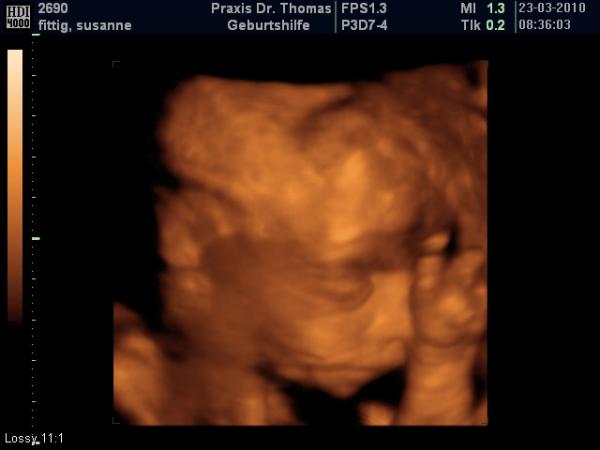

unserem kleinen Mann geht es gut soweit obwohl ich unter vorwehen leide seit dem es wieder stress mit der ex von meinem Mann gab, der Zuckertest war nicht grade angenehm das ganze gepikse dann toko geschrieben und spritze bekommen wegen Rehus negativ und wurde dann doch schließlich mit einem ganz tollen 3 D us belohnt. der Zwerg wiegt jetzt 510 g und ist ca 28 cm groß

könnte ich stunden lang anschauen

ist das nicht ein wunder was man heute so alles von aussen sehen kann? das erleichtert die warterei doch ungemein oder?